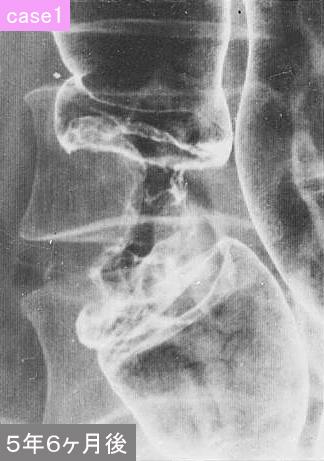

clasificación del pacienteTumor Epitelial Maligno/Adenocarcinoma

parte(separada por órganos)colon/transverso

método de exámenRayos X

clasificación ectoscópica de tumoresTipo 2(Tipo ulcerado de bordes claros)/

diámetro mayor del tumor40 -

grado de penetraciónss(a1)

múltiples tumores(en un mismo órgano)presente(metacrónico)

múltiples tumores(en varios órganos)presente(metacrónico)